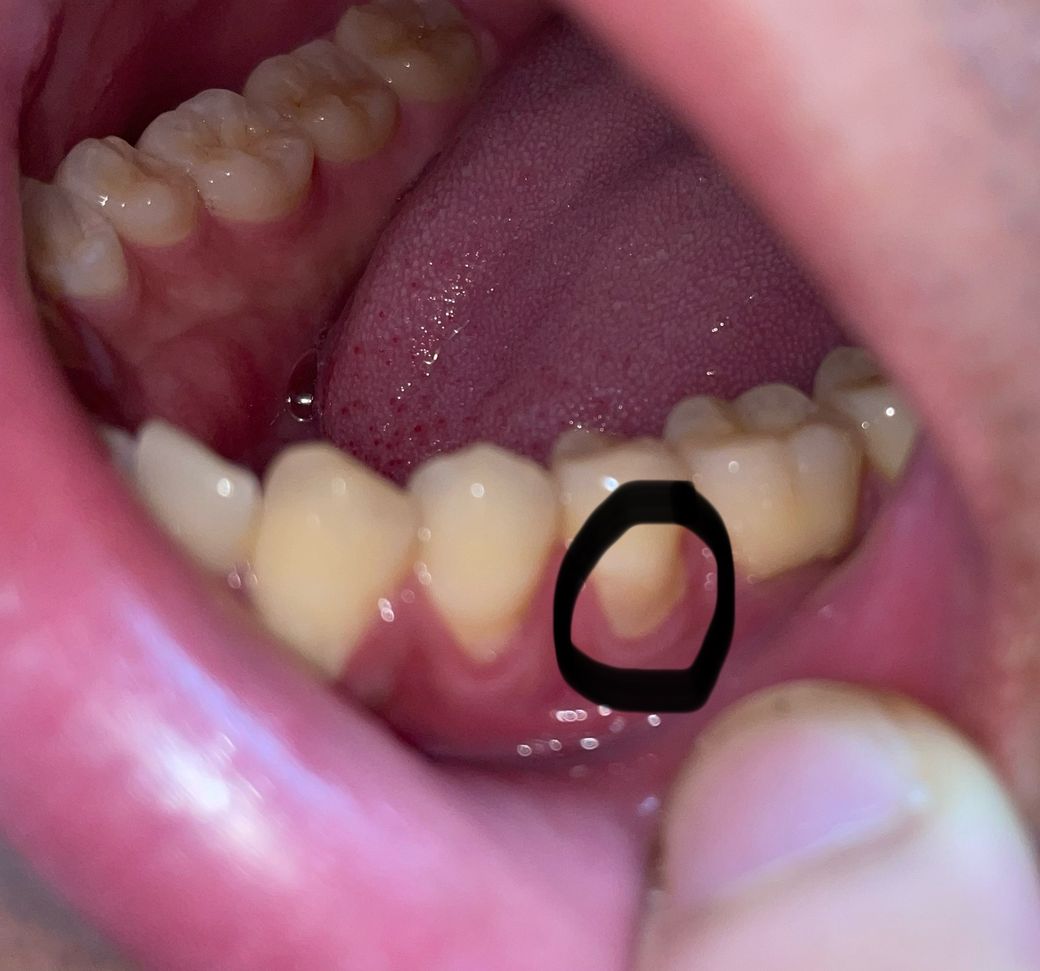

치경부마모증 레진치료를 했는데 마무리가 잘 된건가요?

약 2달전에 동네단골치과에서 치경부마모증 레진으로 치료받았는데 치위생사분이 해주셨습니다. 근데 처음에 딱 치료받았을 땐 치아형태에 맞게 이쁘게 된것처럼 보였는데 오늘 문득 거울 보니까 좀 흘러내린 것처럼 생겼는데 괜찮은건가요?

아니면 시간지나면서 단차가 자연스러워져서 그렇게 보이는건가요? 갑자기 걱정이 되네요... ㅠ

• 1번 째 사진

사진으로 봤을 경우에는 치경부위를 레진으로 충전하고 난다음에 잇몸위로 재료가 덮혀 있는것으로 보입니다.

이런경우 간단하게 치경부레진을 다듬어 줄수 있습니다.

사진으로 봐서는 레진 자체의 문제보다는 치석이 좀 쌓여있는 것 같습니다 치석제거하고 레진 폴리싱하고 다시 봐야 할 것 같습니다